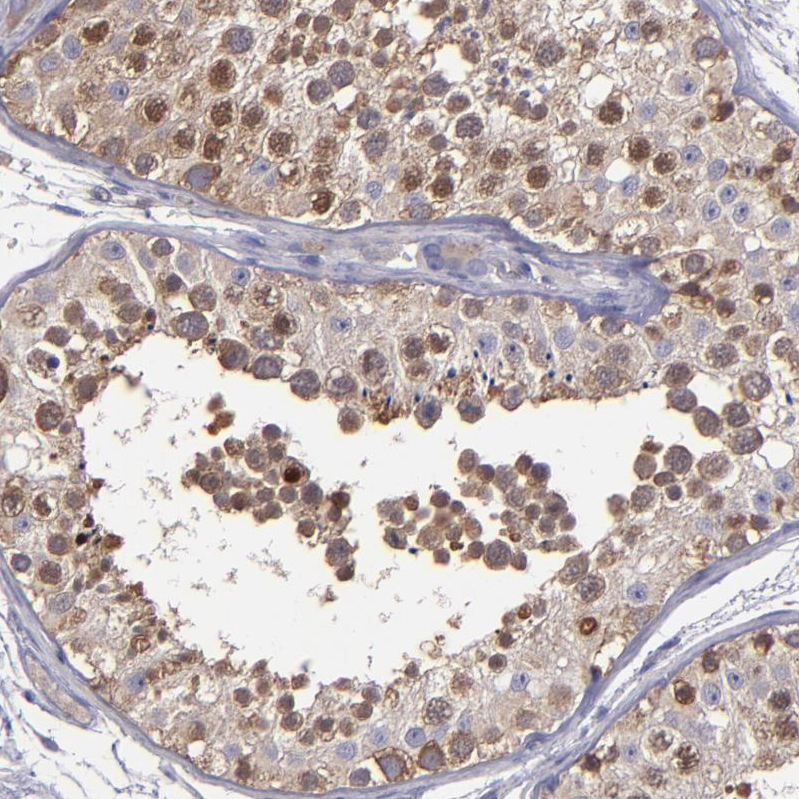

Immunohistochemistry analysis in human cerebral cortex and skeletal muscle tissues using HPA002384 antibody. Corresponding CARS RNA-seq data are presented for the same tissues.